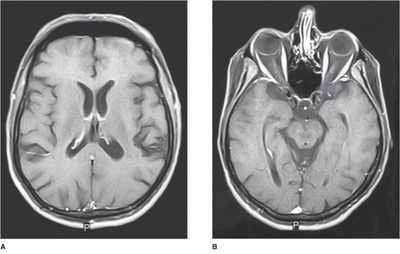

Взрослым людям установить подобный диагноз можно только посредством магнитно-резонансной томографии, которая позволяет получить четкие послойные снимки всех внутренних структур головного мозга. С их помощью можно выделить разные виды оболочек и оценить расстояние между ними, сравнив его с нормой. Кроме этого на томограмме будут видны очаговые и диффузные изменения, вызванные недостатком питания, сдавлением тканей при расширении желудочков мозга и местами усиленного скопления жидкости.

Магнитно-резонансная томография (МРТ) - проводится взрослым и детям старше года. Метод базируется на воздействии магнитных волн, и их обратного отражения в виде электромагнитных импульсов. По результатам обследования определяют структуру тканей головного мозга, химический состав.

При патологии подоболочечного пространства на МР-картине визуализируется:

- расширение ликворных пространств вокруг височных и лобных долей;

- расширение передних межполушарных отделах;

- дилатация желудочков головного мозга (вентрикуломегалия);

- расширения борозд (особенно в задних отделах головного мозга);

- асимметрия черепа.

Расширение субарахноидального пространства на снимке МРТ

При патологии расстояние между оболочками увеличивается, жидкости становится больше, и на МРТ заметно расширение соответствующего межоболочечного пространства, причем, изменения могут носить как локальный, так и диффузный характер.

КТ и МРТ проводятся обычно взрослым пациентам. Эти исследования дорогостоящи, требуют фиксации тела в пространстве, что сложно достичь у грудных детей, а компьютерная томография предполагает рентгеновское излучение, которое несет определенный вред малышам. Кроме того, у взрослых УЗИ не даст нужного объема информации, поэтому им целесообразнее назначать томографию. Если иного выхода нет, и малышу нужна МРТ, то проведут ее под наркозом.

По результату УЗИ или томографии лечащий врач увидит расширение межполушарной щели и субарахноидального пространства, а затем приступит к лечению. Вопрос характера терапии расширенных пространств целиком и полностью определяется первопричиной патологии, ведь само по себе расширение — лишь один из признаков, который невозможно устранить без лечения основного заболевания.

Данная методика дает возможность выявить не только гидроцефалию головного мозга, но и сопутствующие заболевания, точно определить тип патологии. На снимке видны и прямые, и косвенные признаки болезни. К прямым относится увеличение желудочков головного мозга, субарахноидального пространства.